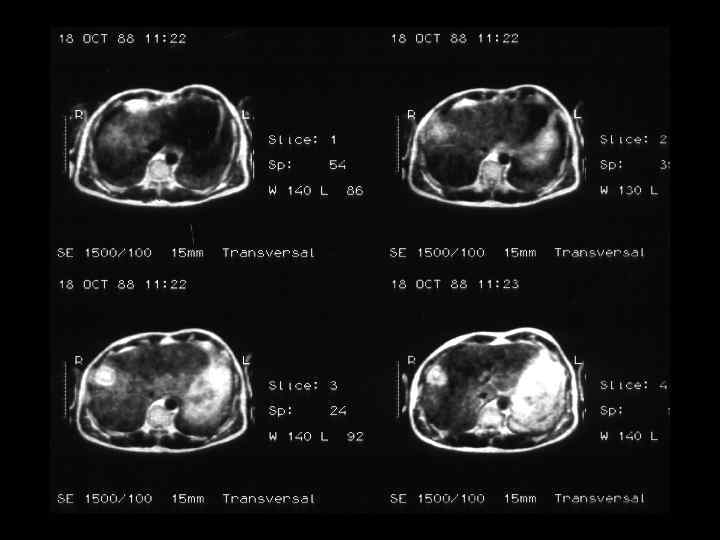

АКТУАЛЬНЫЕ ВОПРОСЫ РЕНТГЕНОЛОГИИ ЛУЧЕВАЯ ДИАГНОСТИКА ОЧАГОВЫХ ПОРАЖЕНИЙ ПЕЧЕНИ Кавернозная гемангиома печени МР- семиотика: - образование с гиперинтенсивным сигналом на Т-2 взвешенном изображении -после введения контрастного вещества- динамика изменений такая же, как при КТ

Клиническое наблюдение. Пациентка С. , 1953 г. р.

Та же пациентка